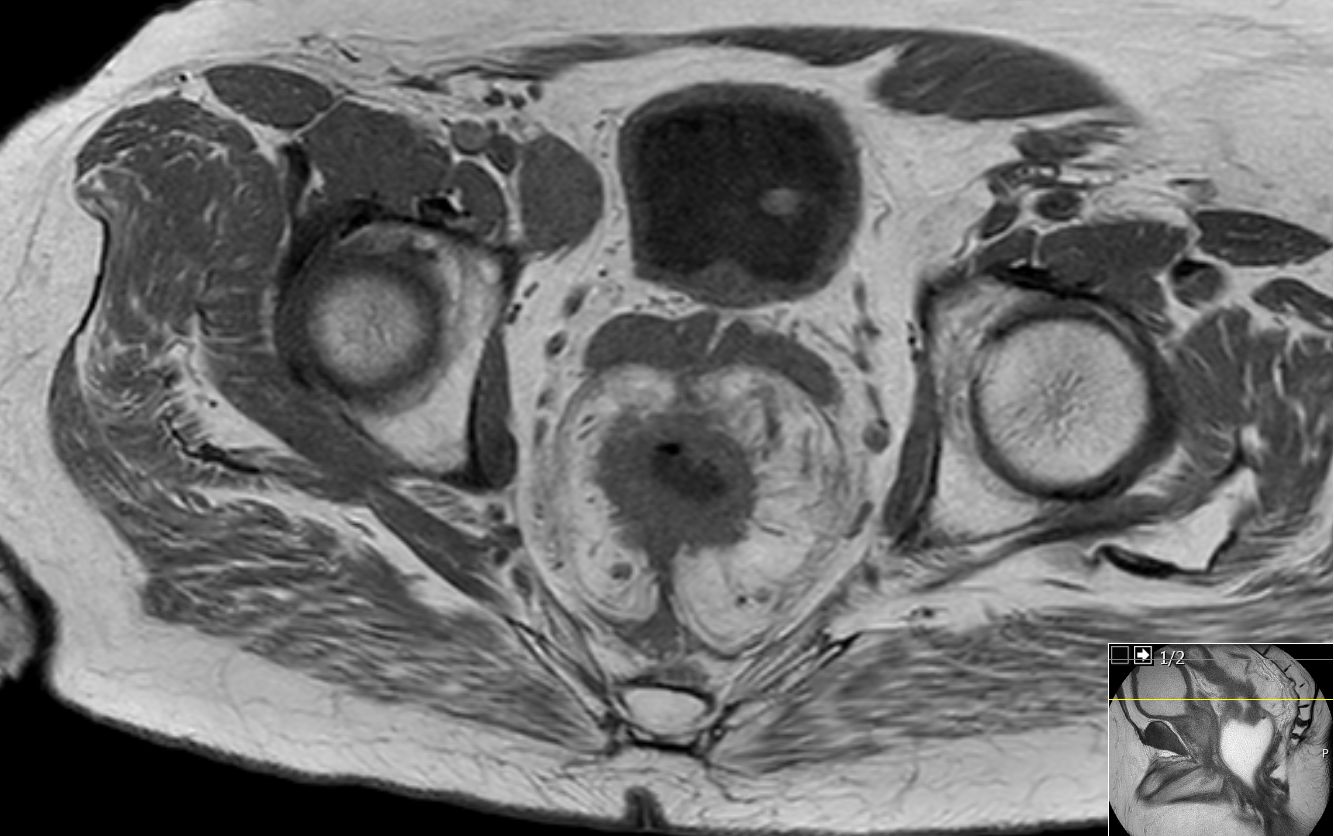

| MRT: T2-Tumor | 61-jähriger Mann mit G2-Adenokarzinom des Rektums von 8-14 cm. T2-Tumor ohne Hinweis auf Wandüberschreitung.![]() |

![]() |